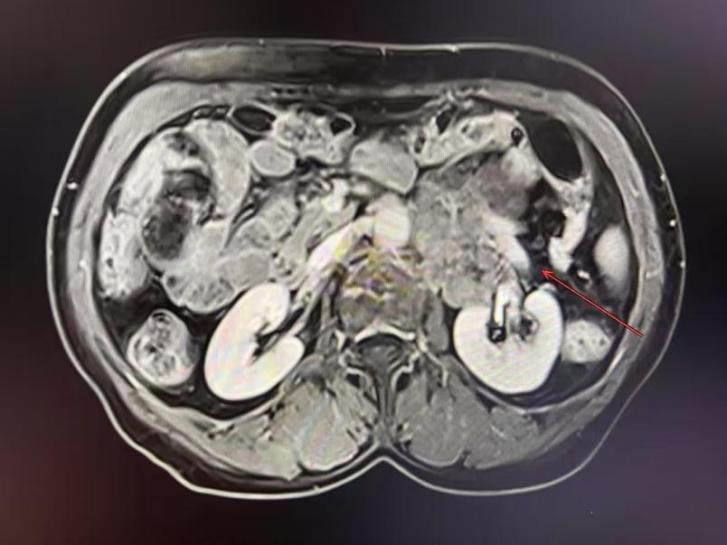

就在厚阿姨一家?guī)缀醴艞墪r(shí),親友推薦她前往中腫甘肅醫(yī)院一試。今年3月,中山大學(xué)腫瘤防治中心婦科熊櫻主任醫(yī)師作為第七批專家進(jìn)駐中腫甘肅醫(yī)院,擔(dān)任中腫甘肅醫(yī)院婦瘤科執(zhí)行主任。接診厚阿姨后,熊櫻主任沒(méi)有輕易否定手術(shù)可能。他帶領(lǐng)婦瘤二科成員仔細(xì)研究病史及影像資料,發(fā)現(xiàn)腫瘤雖然體積巨大,并擠壓腹腔段的主動(dòng)脈及左腎血管,導(dǎo)致血管明顯移位,但尚未完全包裹血管,而且患者無(wú)局部放療史及反復(fù)手術(shù)史。熊櫻主任立即組織多學(xué)科會(huì)診,制定詳細(xì)的手術(shù)預(yù)案。

“鑒于腫瘤與腎血管的密切關(guān)系,不排除術(shù)中發(fā)現(xiàn)腎血管的腫瘤侵蝕?;颊叩母鼓ず竽[瘤與血管的關(guān)系就像藤蔓纏樹(shù),必須一絲一縷地剝離,稍有不慎就會(huì)大出血。”熊櫻主任解釋說(shuō)。甘肅醫(yī)院團(tuán)隊(duì)最終敲定方案:優(yōu)先保證腫瘤切凈,必要時(shí)聯(lián)合左腎切除,但會(huì)盡全力保腎。

手術(shù)當(dāng)日,熊櫻主任主刀,婦瘤二科青年醫(yī)護(hù)團(tuán)隊(duì)通力配合。無(wú)影燈下,腹腔打開(kāi)后,20多公分串珠狀的腫瘤赫然可見(jiàn),將降結(jié)腸、乙狀結(jié)腸系膜高高頂起。熊櫻主任手持手術(shù)電刀,小心翼翼將被覆在腫瘤表面的腸系膜完整游離,保護(hù)了大腸的血供。隨后將腸管及系膜完全翻起,顯露腹膜后的腫瘤。這時(shí)發(fā)現(xiàn)腫瘤緊貼在腹主動(dòng)脈的左側(cè)壁,腫瘤底部已侵犯椎前筋膜和腰大肌,向下延伸至骶岬前及直腸后間隙,向上延伸生長(zhǎng)至左腎血管背側(cè),腫瘤最上級(jí)已超過(guò)腎血管上緣。憑借多年在“血管表面舞蹈”積累下來(lái)的豐富經(jīng)驗(yàn)和精湛技藝,熊櫻主任手中的手術(shù)刀在血管與腫瘤的縫隙間精準(zhǔn)游走,每一步分離都如庖丁解牛,既嚴(yán)格控制了出血,又保證了腫瘤的完整切除。最后在切除左腎血管背側(cè)的腫瘤時(shí),熊櫻主任將左腎完全游離,并將腎臟及血管翻起至對(duì)側(cè),這一“腎反轉(zhuǎn)”的神操作全面暴露腫瘤并完成徹底的切除!